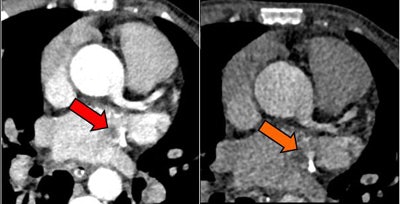

Above, an adult with a left atrial thrombus that was unreported on echocardiography and seen on CT as a filling defect on the arterial (red arrow) and delayed (orange arrow) enhancement phases. Below, an adult with remote inferior myocardial infarction that was unreported on echocardiography and seen on CT as left ventricular inferior myocardial thinning (red arrow). All images courtesy of Dr. Amr Ajlan.Above, an adult with a left atrial thrombus that was unreported on echocardiography and seen on CT as a filling defect on the arterial (red arrow) and delayed (orange arrow) enhancement phases. Below, an adult with remote inferior myocardial infarction that was unreported on echocardiography and seen on CT as left ventricular inferior myocardial thinning (red arrow). All images courtesy of Dr. Amr Ajlan.

CT found five thrombi missed by echocardiography; they were located in the left atrial body, the left atrial appendage, the left ventricular apex, a repaired mitral valve, and the aortic arch. CT did miss a thrombus at the tip of the left atrial appendage that was visualized on echocardiography and seen only retrospectively on CT.